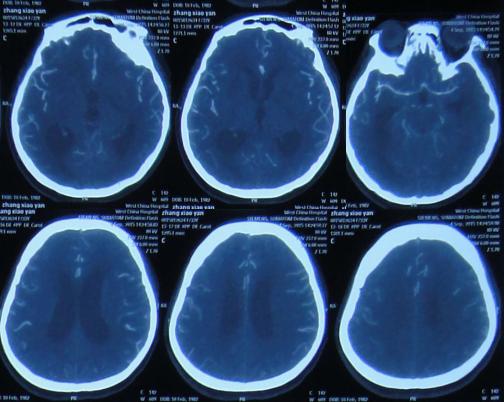

在第2家医院继续腰大池持续引流治疗1个月期间,曾多次查头部CT:2015年10月21日(图-15),2015年10月26日(图-16),2015年11月13日(图-17)均示脑室扩张反而越来越重。

图-15:2015年10月21日头部CT

图-16:2015年10月26日头部CT

图-17:2015年11月13日头部CT